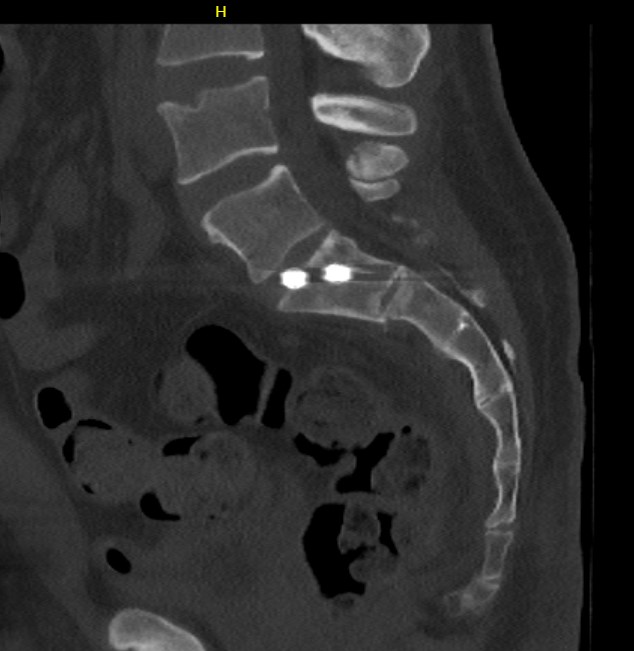

Sacro-iliac screws

Guide wire insertion into body of S1

- anatomic safe zone

- between S1 foramen and superior ala on outlet view (outlet view)

- between neural canal and anterior body (inlet view)

Insert 6.5 mm partially threaded cannulated screw, to aid compression

Check screw position with CT